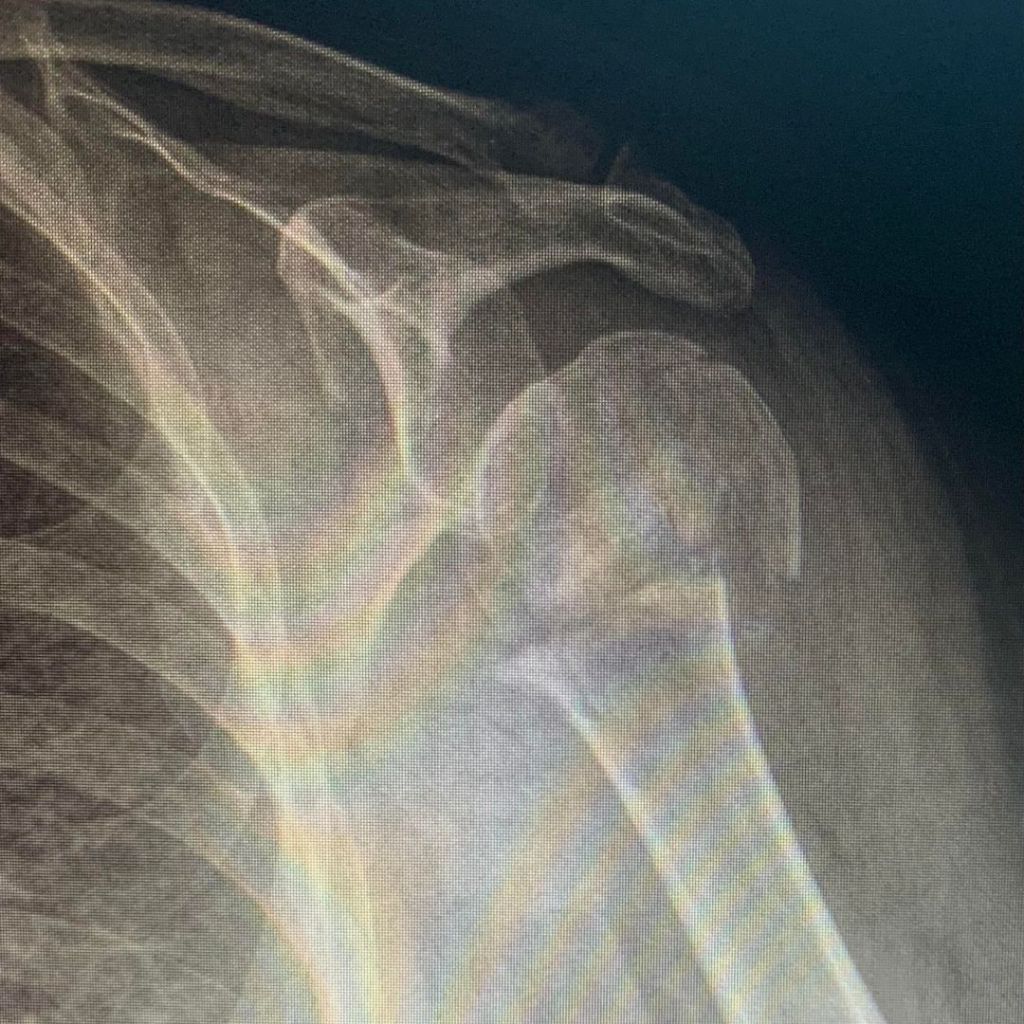

Os presentamos un caso tratado en Trauma Sport con Magnetoterapia. Paciente de 74 años que sufre una caída desde su propia altura generando una fractura de baja energía a nivel del cuello del húmero, en el hombro izquierdo. Acude a nuestra clínica en Ourense 3 meses después del diagnóstico con una imagen radiológica (Fig. 1) en la que vemos claramente como la fractura no ha consolidado; y con el tiempo tanscurrido puede considerarse un retardo de consolidación. La paciente no podía retirar el cabestrillo, tenía dolor que no calmaba con tratamientos convencionales, además de dificultad para el descanso nocturno.Angustiada a su vez, porque le habían comentado que dado que no había pegado la fractura deberían someterla a una cirugía con placa y tornillos, e injerto óseo.